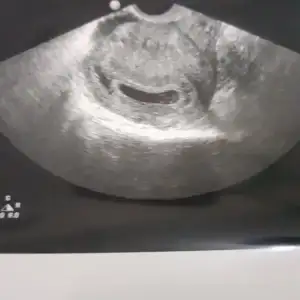

Oy maşallah kuzuyaSürpriz sürpriz sürpriz !!! Öncelikle hepinize dualarınız için teşekkür ederim. Hoca 2li tarama yapmadı (yaş 36 oldugu için sonuç illa ki olumsuz çıkar dedi) Aynı gün genetik bölümünden konsültasyon istedi( onlar da onaylarsa 1 ay sonraki muayenede amniyosentez yapalım dedi)

Onun dışında bebişim çok iyi, kese arkası kanamam da sonlanmış, elleri ayakları agzı burnu her yeri net görülüyor. ..

Fotoğrafınız var mı annesi